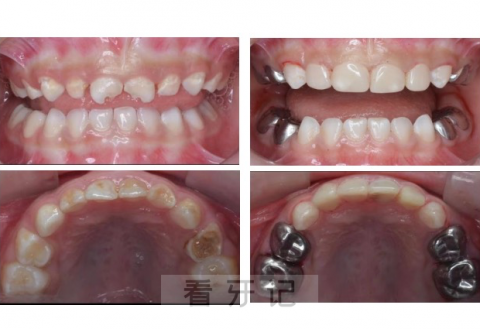

在乳牙缺损较大,难以充填或严重磨耗及龋齿治疗完成后,医生会做一个“小牙冠”套在患牙上,可以保护牙齿并加强牙齿的强度,能够确保乳牙正常健康地被恒牙替换。这种牙冠叫做乳牙预成冠。后牙通常采用不锈钢金属牙冠,前牙为了美观,则采用透明牙冠修复。

乳牙预成冠技术是一项非常成熟的技术,有充分的研究证据表明它的疗效要优于单纯的充填,在发达国家,乳牙治疗中预成冠的使用可达到80%。因此预成冠本身的安全性和稳定性是十分可靠的。